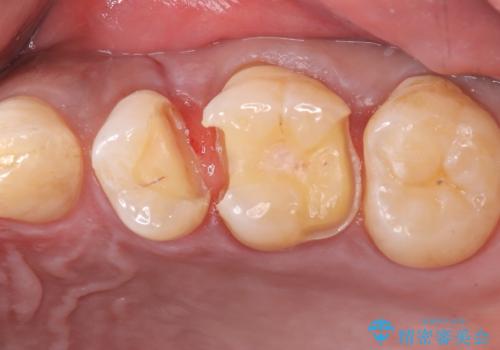

左上5番目の歯の側面に実質欠損を認め、隣の6番目の歯にも虫歯を認めたため両歯ともセラミックインレーでの治療となりました。

左上5番遠心に実質欠損を認め、さらに5番と6番の隣接面にもカリエスを認めました。6番の咬合面には、元々コンポジットレジン修復が施されており、劣化がみられたのでその部分も含め修復することとなりました。

セラミックインレーセット時は、ラバーダム防湿を行っています。